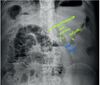

Primeiro exame a ser solicitado na suspeita de abdome agudo obstrutivo?

Raio-x em 3 incidências Achado: empilhamento em moedas (intestino delgado >> obstrução alta)